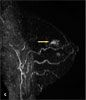

For 6 weeks, a 68-year-old woman had had sharp pain in the left breast that radiated to the left arm and back. The pain was worse on palpation; ibuprofen provided only mild relief. She denied nipple discharge, skin discoloration, and fever. She had no family history of breast cancer. Results of a biopsy of the left breast 6 years earlier were benign. Her most recent mammogram (A), 4 weeks earlier, was negative.

Cardiac, lung, and abdominal findings were normal. A tender 0.5-cm cyst was noted at the 12 o'clock position. There were no palpable lymph nodes, discharge, skin retraction, or erythema. An ultrasonogram of the left breast showed no suspicious lesions (B). Despite the previous negative findings, breast cancer was strongly suspected. The patient underwent MRI of the left breast, which showed a 1 3 3-cm mass at the 12 o'clock position and another lesion at the 4 o'clock position (C). Subsequent biopsy results revealed high-grade ductal carcinoma in situ (DCIS). The breast surgeon recommended a left total mastectomy and sentinel node biopsy, with possible axillary dissection. Excision of a papilloma found in the right breast on MRI was also recommended because core biopsy results showed atypical features.